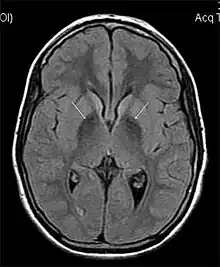

MRI hypointensity (white arrows) in the globus pallidi that indicates the presence of iron deficiencies which would be seen in a diagnosis of Aceruloplasminemia | |

Diagnosis of this disorder depends on blood tests demonstrating the absence of serum ceruloplasmin, combined with low serum copper concentration, low serum iron concentration, high serum ferritin concentration, or increased hepatic iron concentration. MRI scans can also confirm a diagnosis; abnormal low intensities can indicate iron accumulation in the brain.[5]